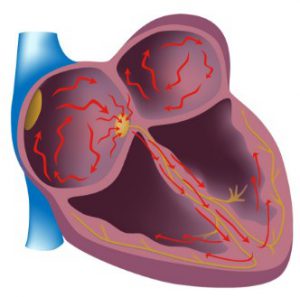

Részt vesz a gyulladásos válasz lehet bármely réteg a szív:

- A belső bevonatának a szív a immunológiai gyulladás hívják endocarditis.

- Gyulladásos elváltozások a külső héj hívják pericarditis.

- Ha az eljárás során a szívizom, a szívbetegségek nevet kap szívizomgyulladás.

Minden ilyen rendellenességek agresszív fertőzések és a nem megfelelő kezelés lehet visszafordíthatatlan természetesen. Vírusos vagy fertőző mikroorganizmusok vándorolnak át a véráramba, amely magában foglalja a folyamat az új szerveket. Veszélyes fertőzés a szelepek, amelyek kezdik, hogy nem működik, adja át a teljes része a vér vissza elfog néhány összeget. Ilyen esetekben, gyulladásos szívbetegség meghatározza a növekedése a terhelés rajta, provokál dilatáció és hipertrófia a szív osztály.